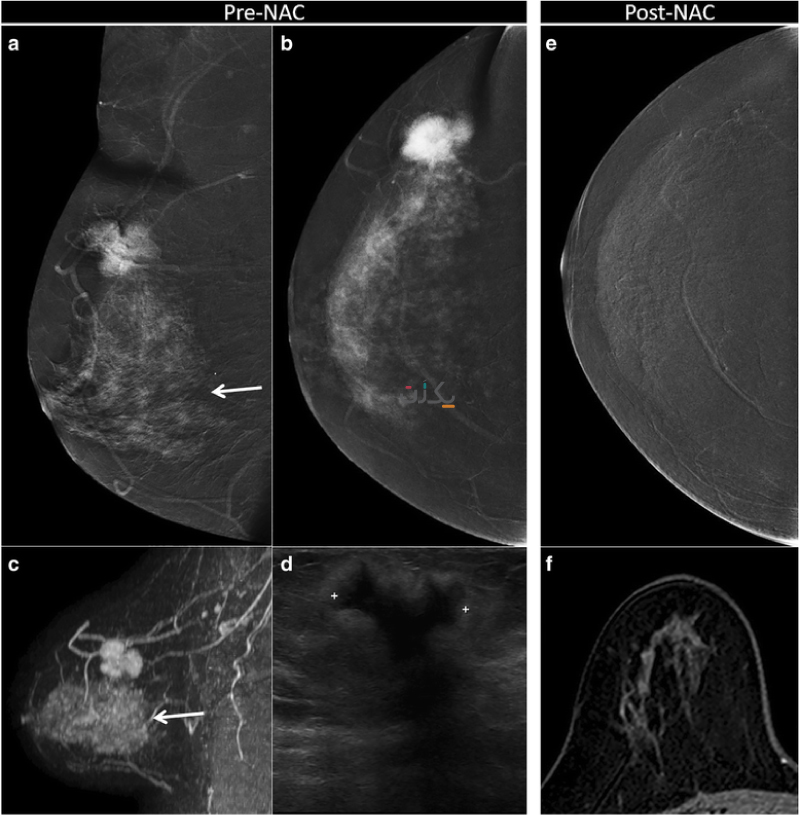

در ماموگرافی نقاط کلسیفیه (متراکم و ناهنجار ) به صورت نقاط سفید و چربی به رنگ خاکستری دیده می شود. این ناهنجاری ها در افراد سالمند به دلیل بافت چربی که این افراد دارند، راحت تر دیده می شوند. کیست های خوش خیم معمولا گردن و دیواره های منظم دارند اما توده های بدخیم نامنظم هستند. ولی برای اطمینان از خوش خیم یا بدخیم بودن آن باید سونوگرافی نیز انجام شود.

سیستم تشخیص بین المللی ماموگرافی BI RADS نام دارد و مراحل مختلفی دارد که طبق این مراحل پزشک تصمیم می گیرد که پیگیری بعدی به چه صورت باشد مثلا نیاز به عکس برداری مجدد هست یا نه.